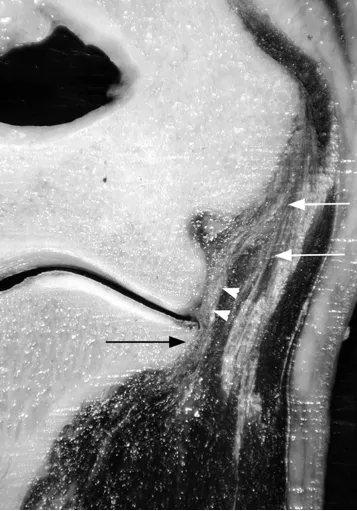

(a)33 岁女性受试者的矢状位 T2 加权磁共振成像,以及(b)对应的示意图,清晰显示出后外侧滑膜皱襞的前后径(白色箭头所示)与头尾径(黑色箭头所示)。图中 AM 代表肘肌。

(c)与图 a 相同的磁共振影像,以及(d)对应的示意图,显示出肱骨小头的假性缺损(箭头所示),及其与后外侧滑膜皱襞的密切关联。图中 AM 代表肘肌。